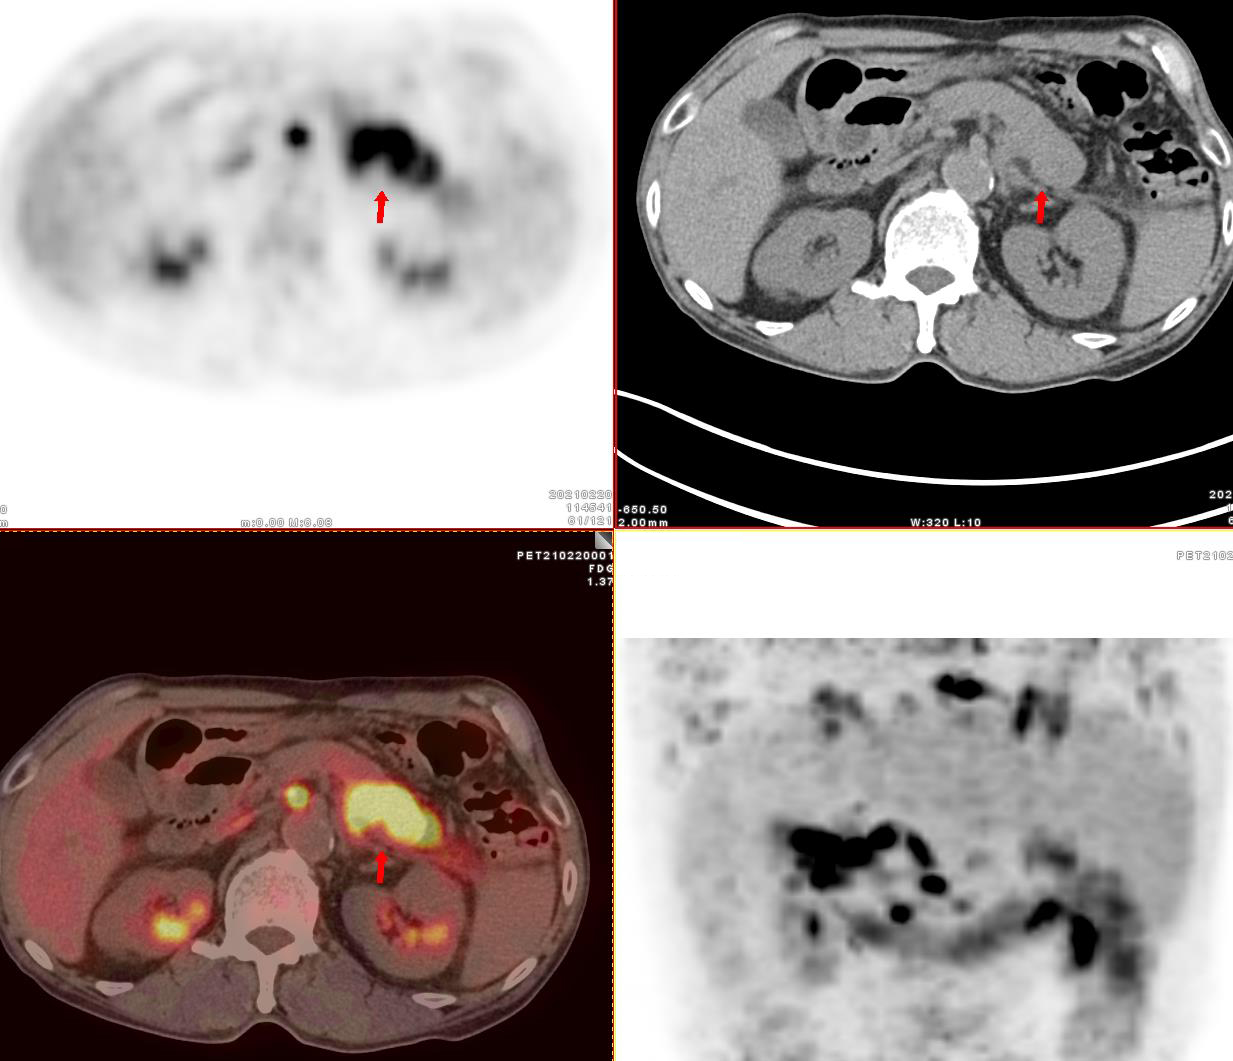

檢查后發(fā)現(xiàn)郭老伯的胰腺體尾部增大,放射性攝取異常增高,SUVmax 9.5。雙肺內(nèi)彌漫分布大小不等結(jié)節(jié),放射性攝取增高,SUVmax 6.1。全身多發(fā)骨質(zhì)破壞,放射性攝取增高,SUVmax 8.5。雙側(cè)鎖骨區(qū)、網(wǎng)膜囊、腹膜后及右側(cè)膈腳后間隙多發(fā)增大淋巴結(jié),放射性攝取增高,SUVmax 12.1。

影像科醫(yī)生考慮為:胰腺癌并雙肺轉(zhuǎn)移,多發(fā)骨轉(zhuǎn)移,多發(fā)淋巴結(jié)轉(zhuǎn)移

PET/CT示胰腺體尾部腫瘤代謝增高